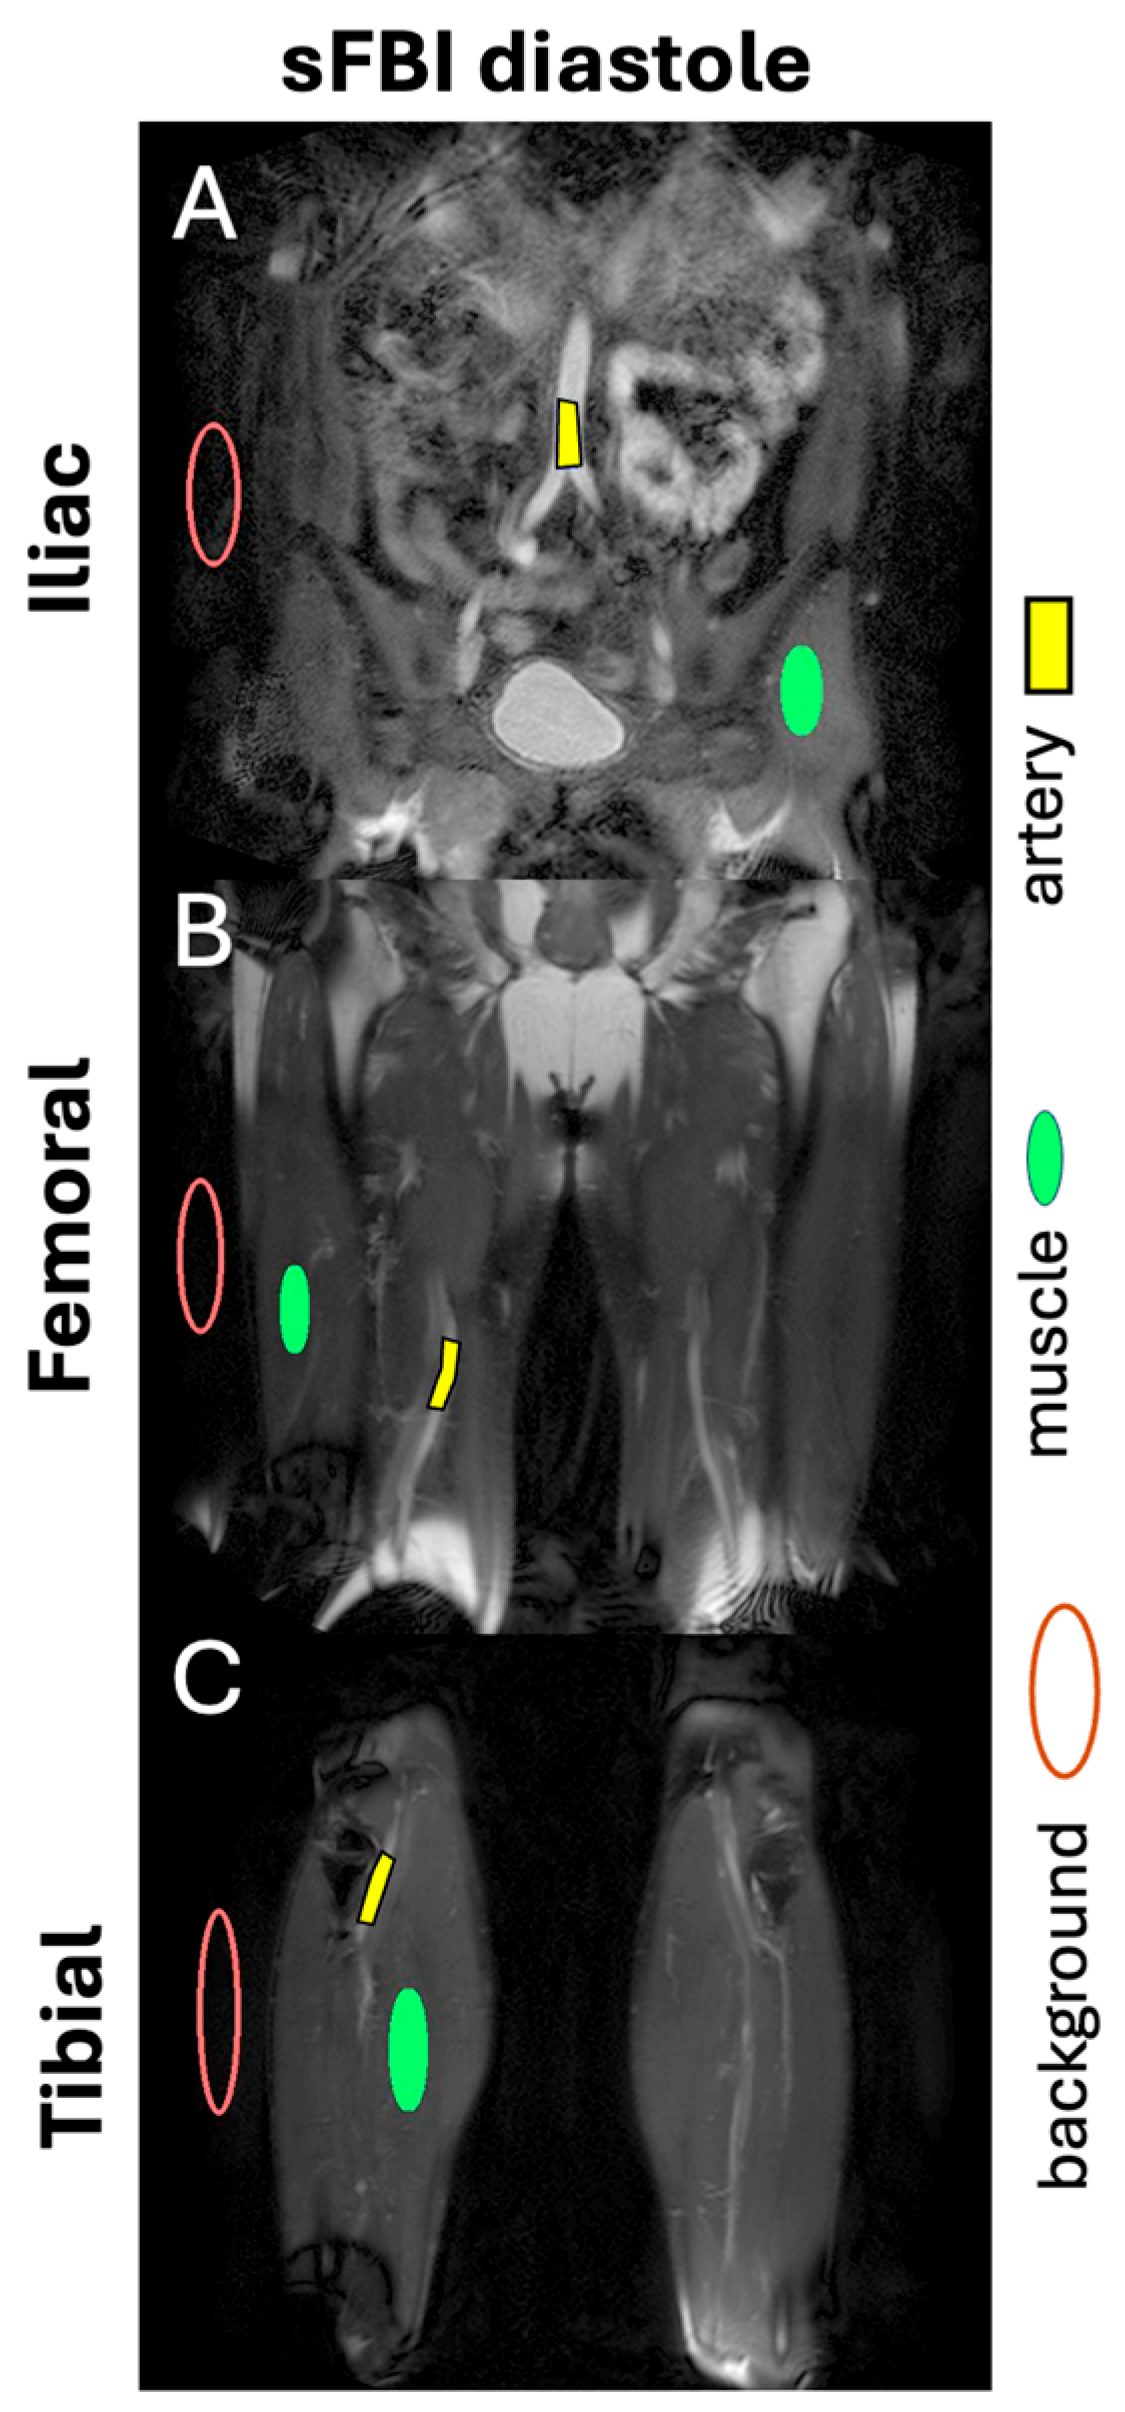

- Malis, V.; Vucevic, D.; Bae, W.C.; Yamamoto, A.; Kassai, Y.; Lane, J.; Hsiao, A.; Nakamura, K.; Miyazaki, M. Fast Non-contrast MR Angiography Using a Zigzag Centric k(y) − k(z) k-space Trajectory and Exponential Refocusing Flip Angles with Restoration of Longitudinal Magnetization. Magn. Reson. Med. Sci. 2025, 24, mp-2023. [Google Scholar] [CrossRef] [PubMed]

- Bae, W.C.; Hahn, L.; Malis, V.; Mesa, A.; Vucevic, D.; Miyazaki, M. Peripheral Non-Contrast MR Angiography Using FBI: Scan Time and T2 Blurring Reduction with 2D Parallel Imaging. J. Imaging 2024, 10, 223. [Google Scholar] [CrossRef] [PubMed]